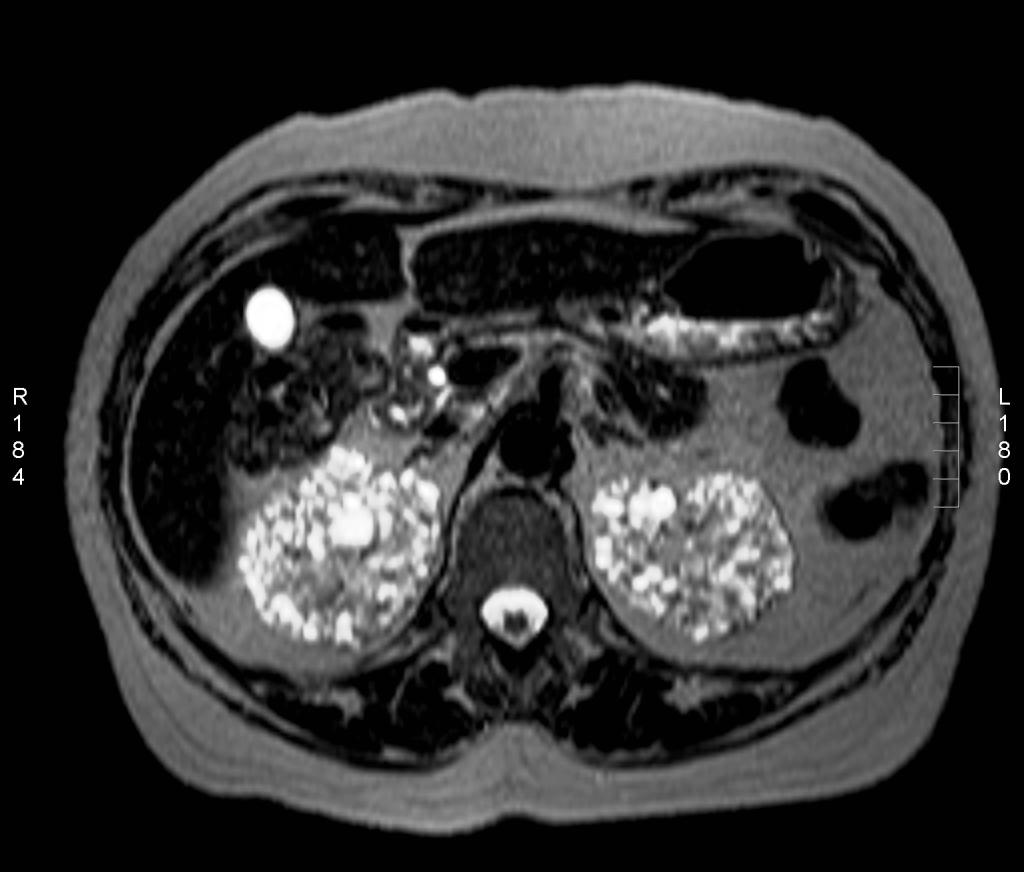

Een 57-jarige vrouw met hypothyreoïdie kwam ter controle op de polikliniek Interne Geneeskunde. Zij werd behandeld met levothyroxine. Verder had zij een bipolaire stoornis waarvoor ze al meer dan 15 jaar lithium gebruikte. Haar reeds bestaande nierfunctiestoornis verergerde: laboratoriumonderzoek toonde een serumconcentratie creatinine van 170 μmol/l en een geschatte glomerulaire filtratiesnelheid van 39 ml/min (volgens de ‘modification of diet in renal disease’(MDRD)-formule). Bij echografie zagen we multipele kleine cysten in beide nieren. De niergrootte was niet-afwijkend en er was geen stuwing te zien. Bij MRI-onderzoek werden in beide nieren zowel corticaal als medullair multipele cysten gezien, waarvan de meeste 1-2 mm groot waren (klik op de afbeelding voor volledige weergave).